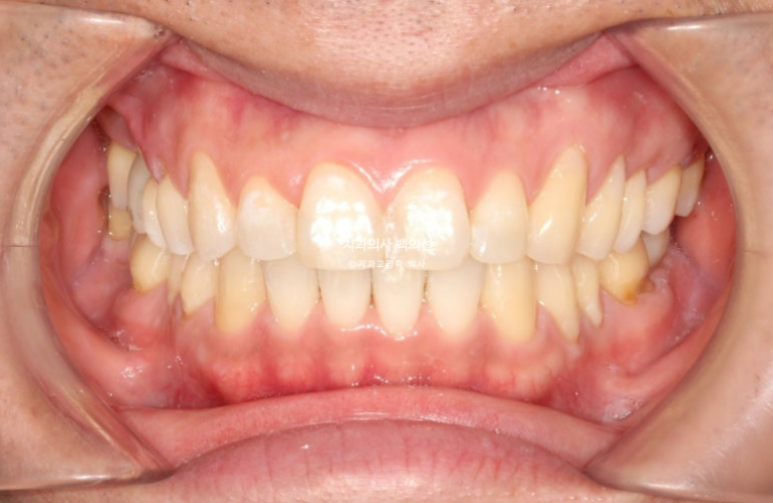

결과 보겠습니다.

25.06

이제 전 후 비교 보겠습니다.

임플란트는 아름답게 심어졌고 사랑니 교합도 좋습니다.

아랫입술과 평행한 적절한 스마일라인

깔끔한 앞니각도